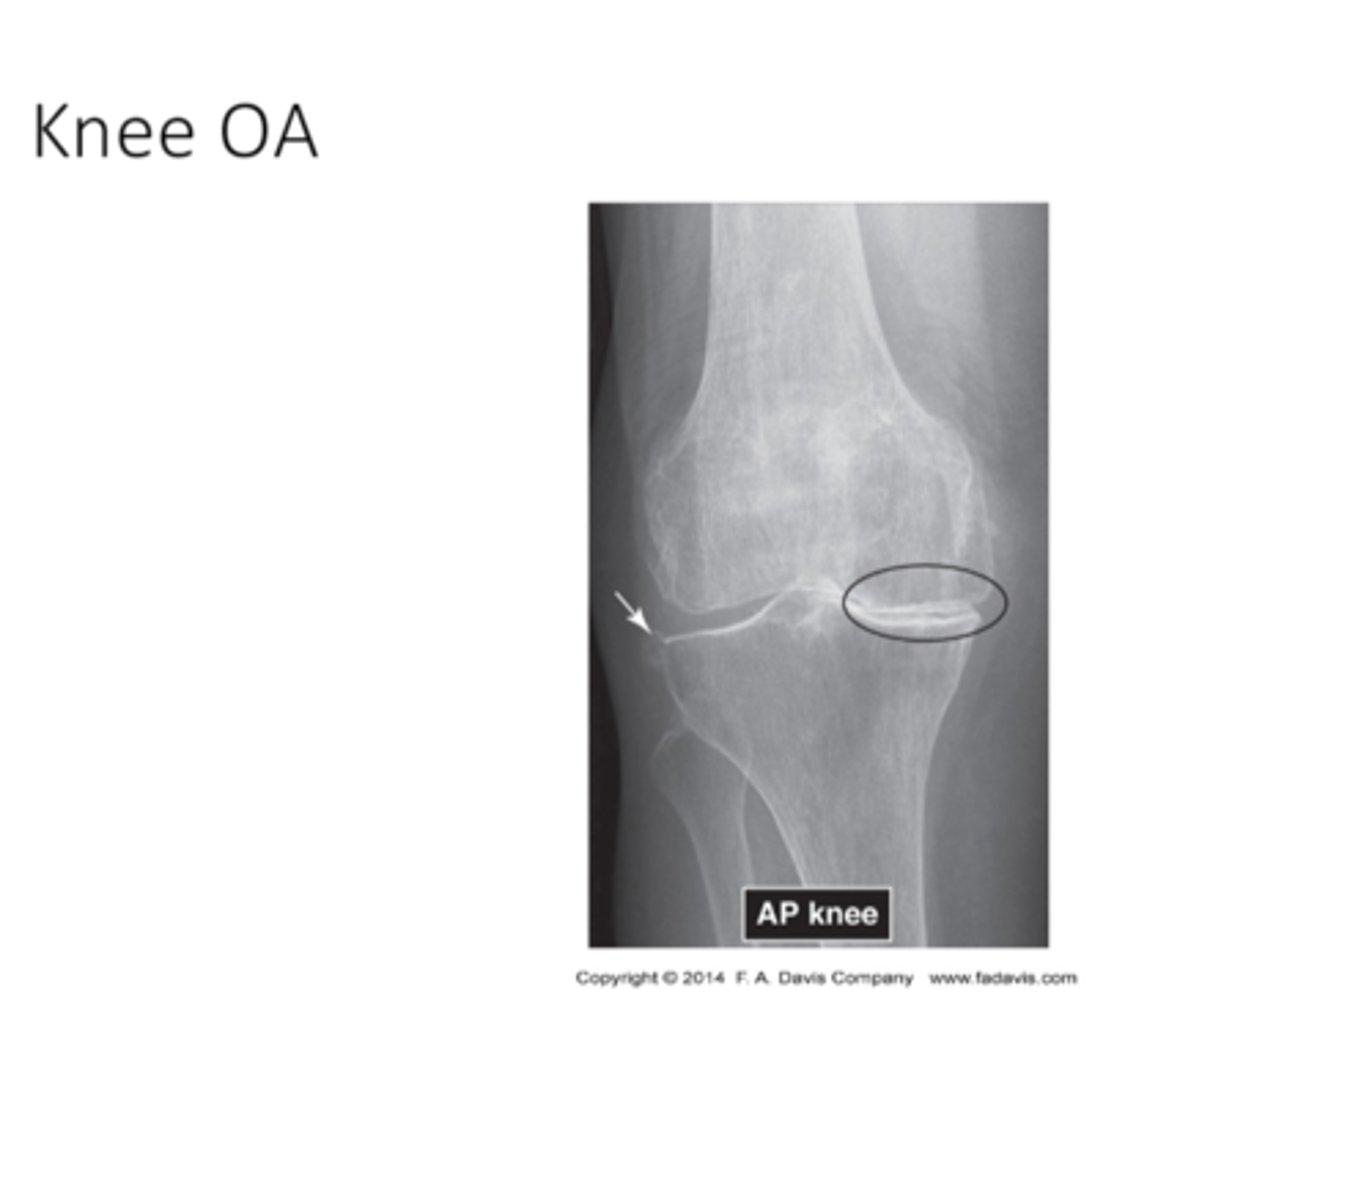

what does knee OA look like

what does Excessive Sclerosis look like